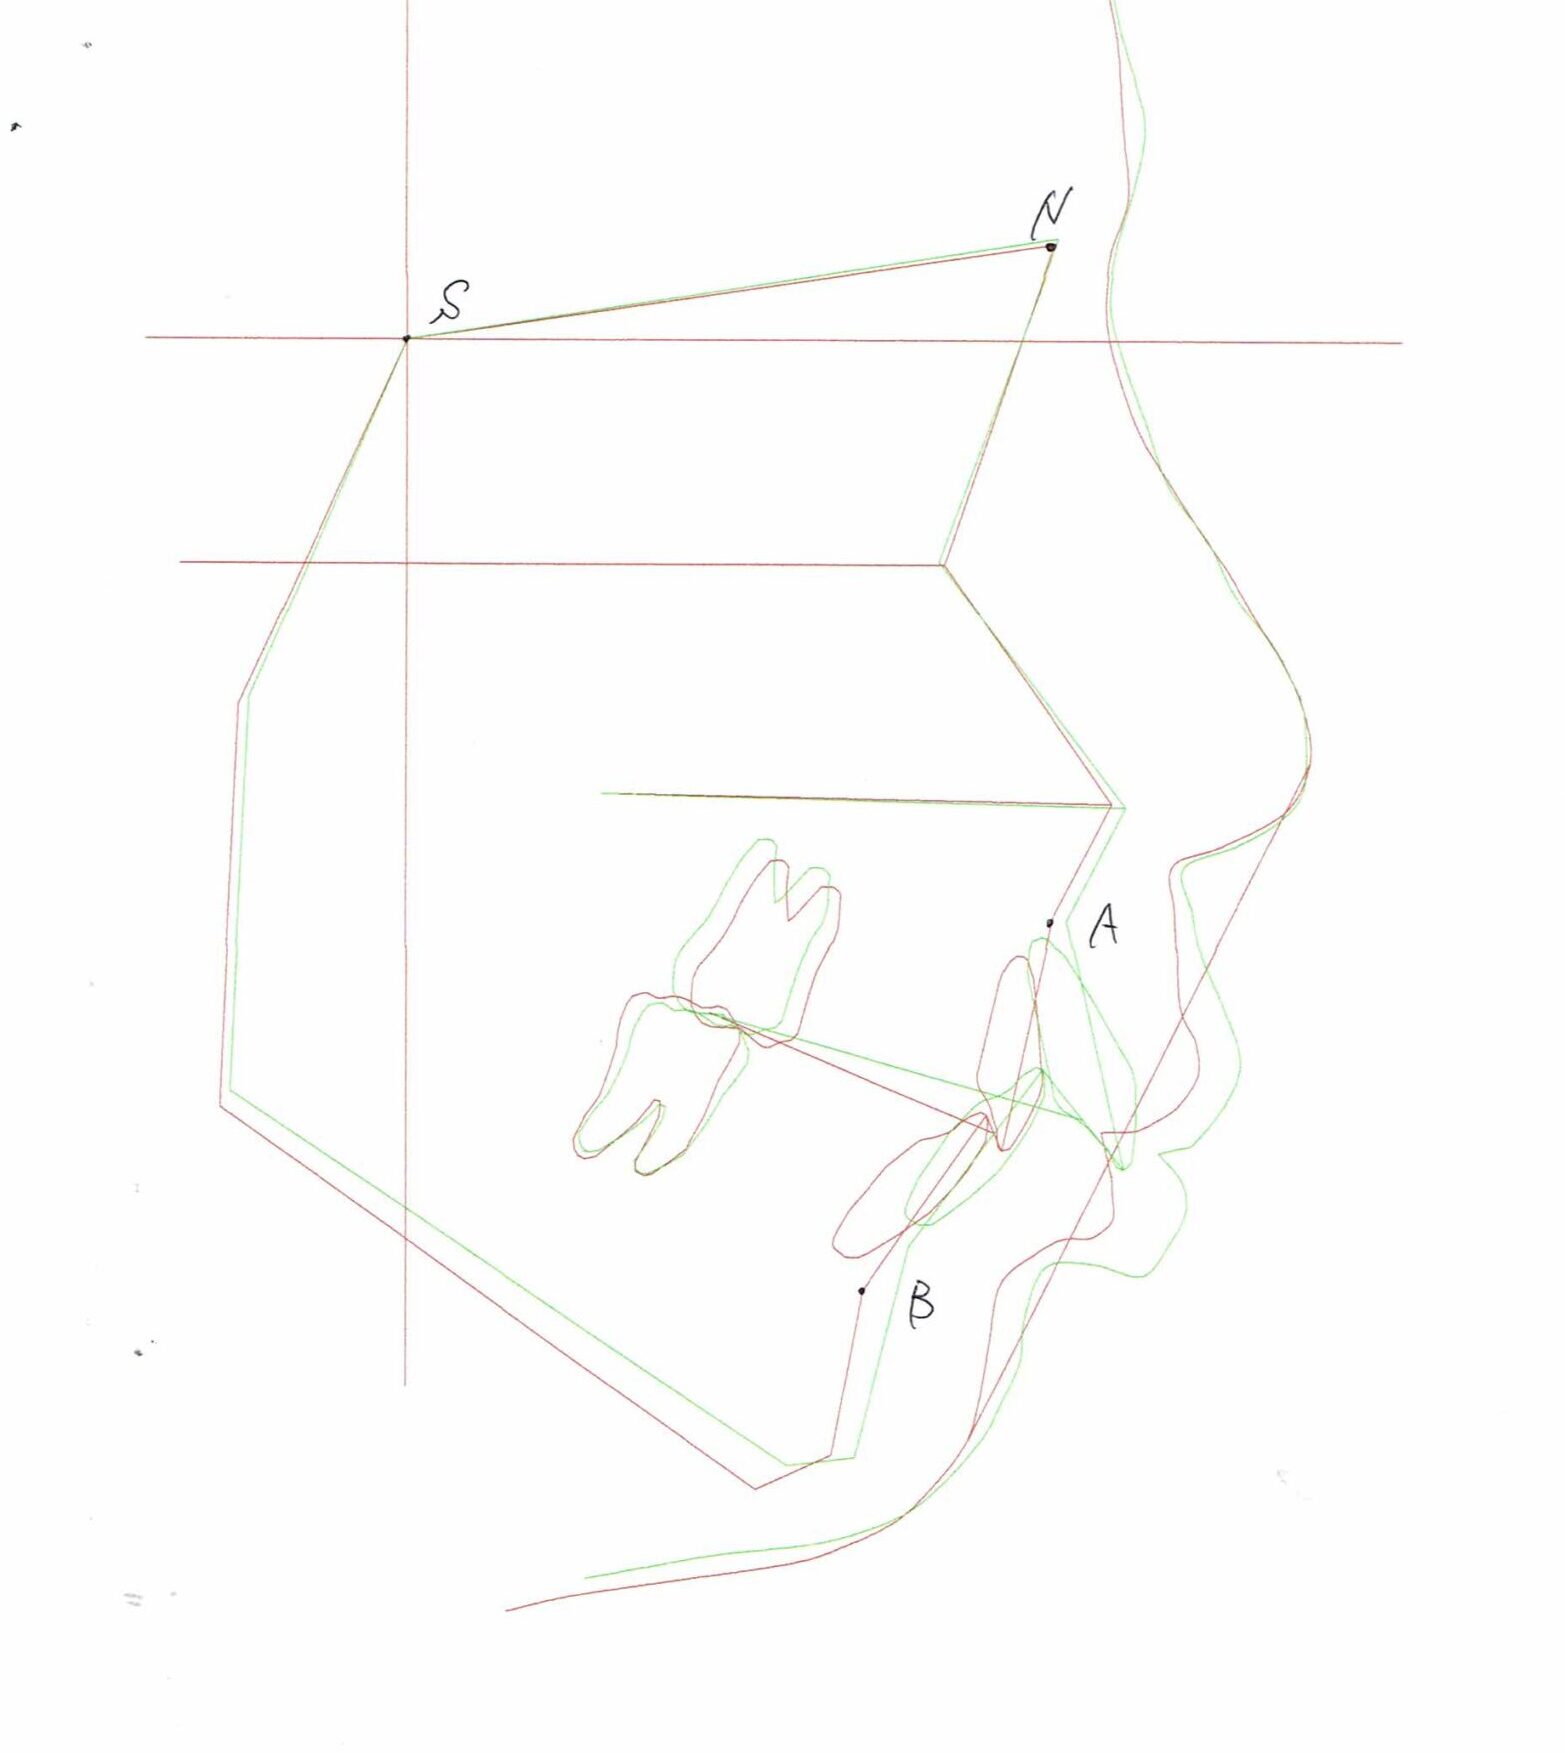

セファログラムのトレースの重ね合わせ(緑:治療前、赤:治療終了時)

治療前後の解説

| 治療前 | でこぼこしている歯による歯磨きのやりにくさや、奥歯がしっかり咬んでいない鋏状咬合(すれ違い咬合)。 出っ歯による口の閉じにくさ(口唇閉鎖不全)と、正面から見た時のオトガイ部にできる梅干し様のシワやイーラインから飛び出た口元(口ゴボ)。 機能面も審美面も気にしていた患者さんです。 治療中もなるべく装置を目立たせたくないため、ハーフリンガルでの治療となりました。 |

| 治療後 | 上下の歯がお互いにはまり込み、全体的に緊密な咬み合わせになっています。 出っ歯が治り、口元の突出感が改善されて綺麗なEラインを獲得しました。 すれ違い咬合や叢生(歯のでこぼこ)も治って歯磨きがしやすく、嚙みやすい状態になっています。 |